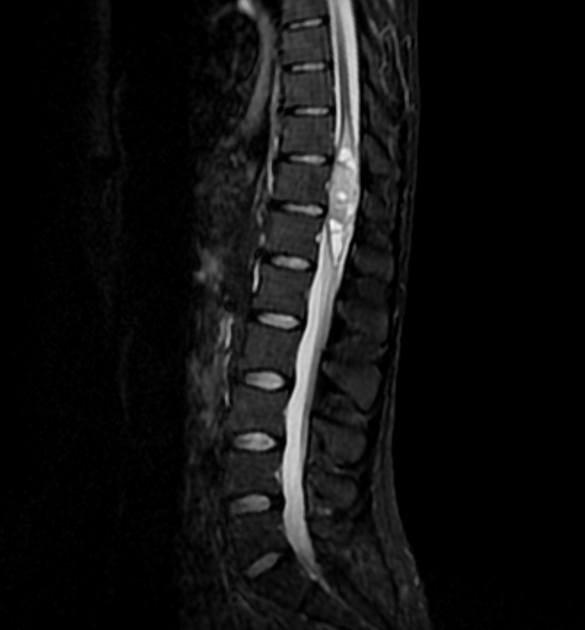

U màng nội tủy

» Thông tin: Nữ giới – 35 tuổi.

» Lâm sàng: Yếu chi dưới.

# U màng nội tủy nhầy nhú (Myxopapillary Ependymoma).